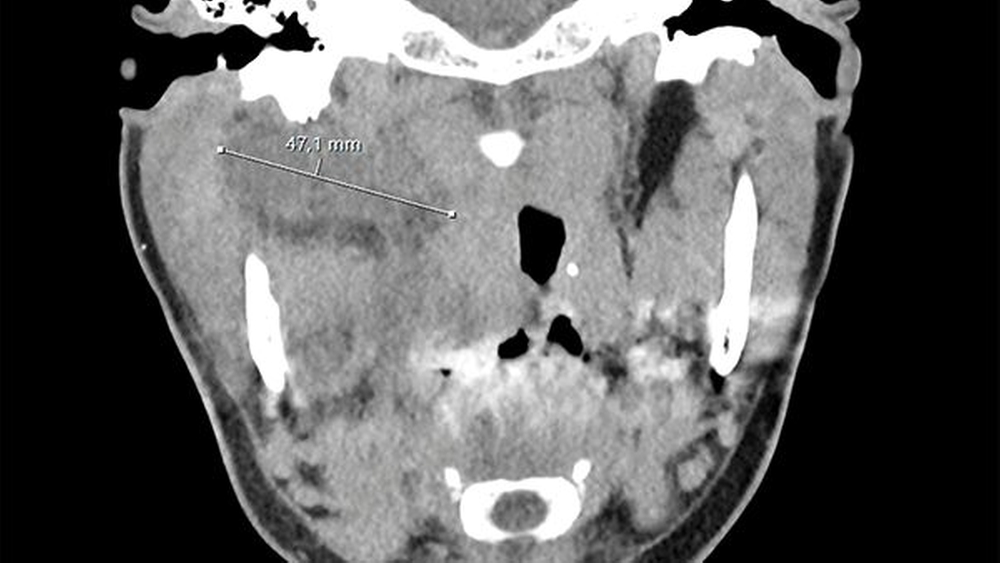

Sonografisch ließ sich weder von submandibulär noch von temporal eine klar abgrenzbare Abszessformation darstellen. Ein initial angefertigtes Labor zeigte stark erhöhte Entzündungsparameter mit einem C-reaktiven Protein von 261 mg/l (Normwert < 5 mg/l) sowie einer Leukozytose von 18/nl (Normwert 3,5–10/nl). Zur weiteren Diagnostik erfolgte die Anfertigung einer Computertomografie des Schädels mit Kontrastmittel. Hier zeigte sich eine circa 14 mm x 45 mm große, liquide Veränderung rechts im Musculus Pterygoideus mediales bis in die Glandula Parotis rechts reichend (Abbildungen 1 und 2). Aufgrund einer flauen Parenchymkontrastierung ließ sich eine Abszessformation nicht sicher ausschließen, die Befunde sprachen in Zusammenschau mit dem zeitlichen Ablauf und der stattgefundenen zahnärztlichen Behandlung jedoch in erster Linie für ein postinterventionelles Hämatom. Eine antikoagulatorische und/oder thrombozytenaggregatorische Therapie konnte ausgeschlossen werden.